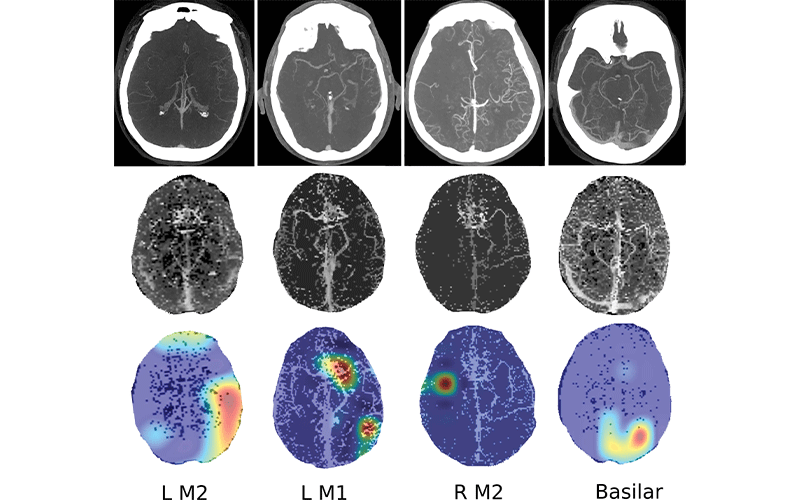

Images show four separate patients with large vessel occlusions correctly predicted by the algorithm. The top row shows a representative CT slice from the delayed venous phase CT angiography. The middle row shows the preprocessed maximum intensity projection images that function as the input to the model. The bottom row are overlaid heat maps, with areas in red showing the most discriminative regions. Notice these so-called hot regions correlate with the occlusion location (respectively: left [L] M2, L M1, right [R] M2, basilar) in each patient.